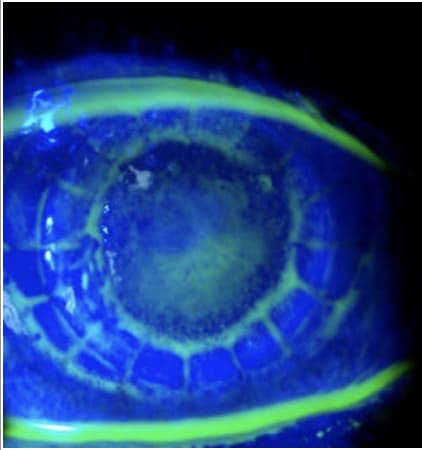

Scleral lenses completely vault the cornea, facilitating the fitting of a complex corneal shape.

Fitting tip. A central clearance of 200 µm and limbal vault of 50 µm promotes adequate corneal oxygenation.1 Optimize patient comfort by customizing lens haptics. OM